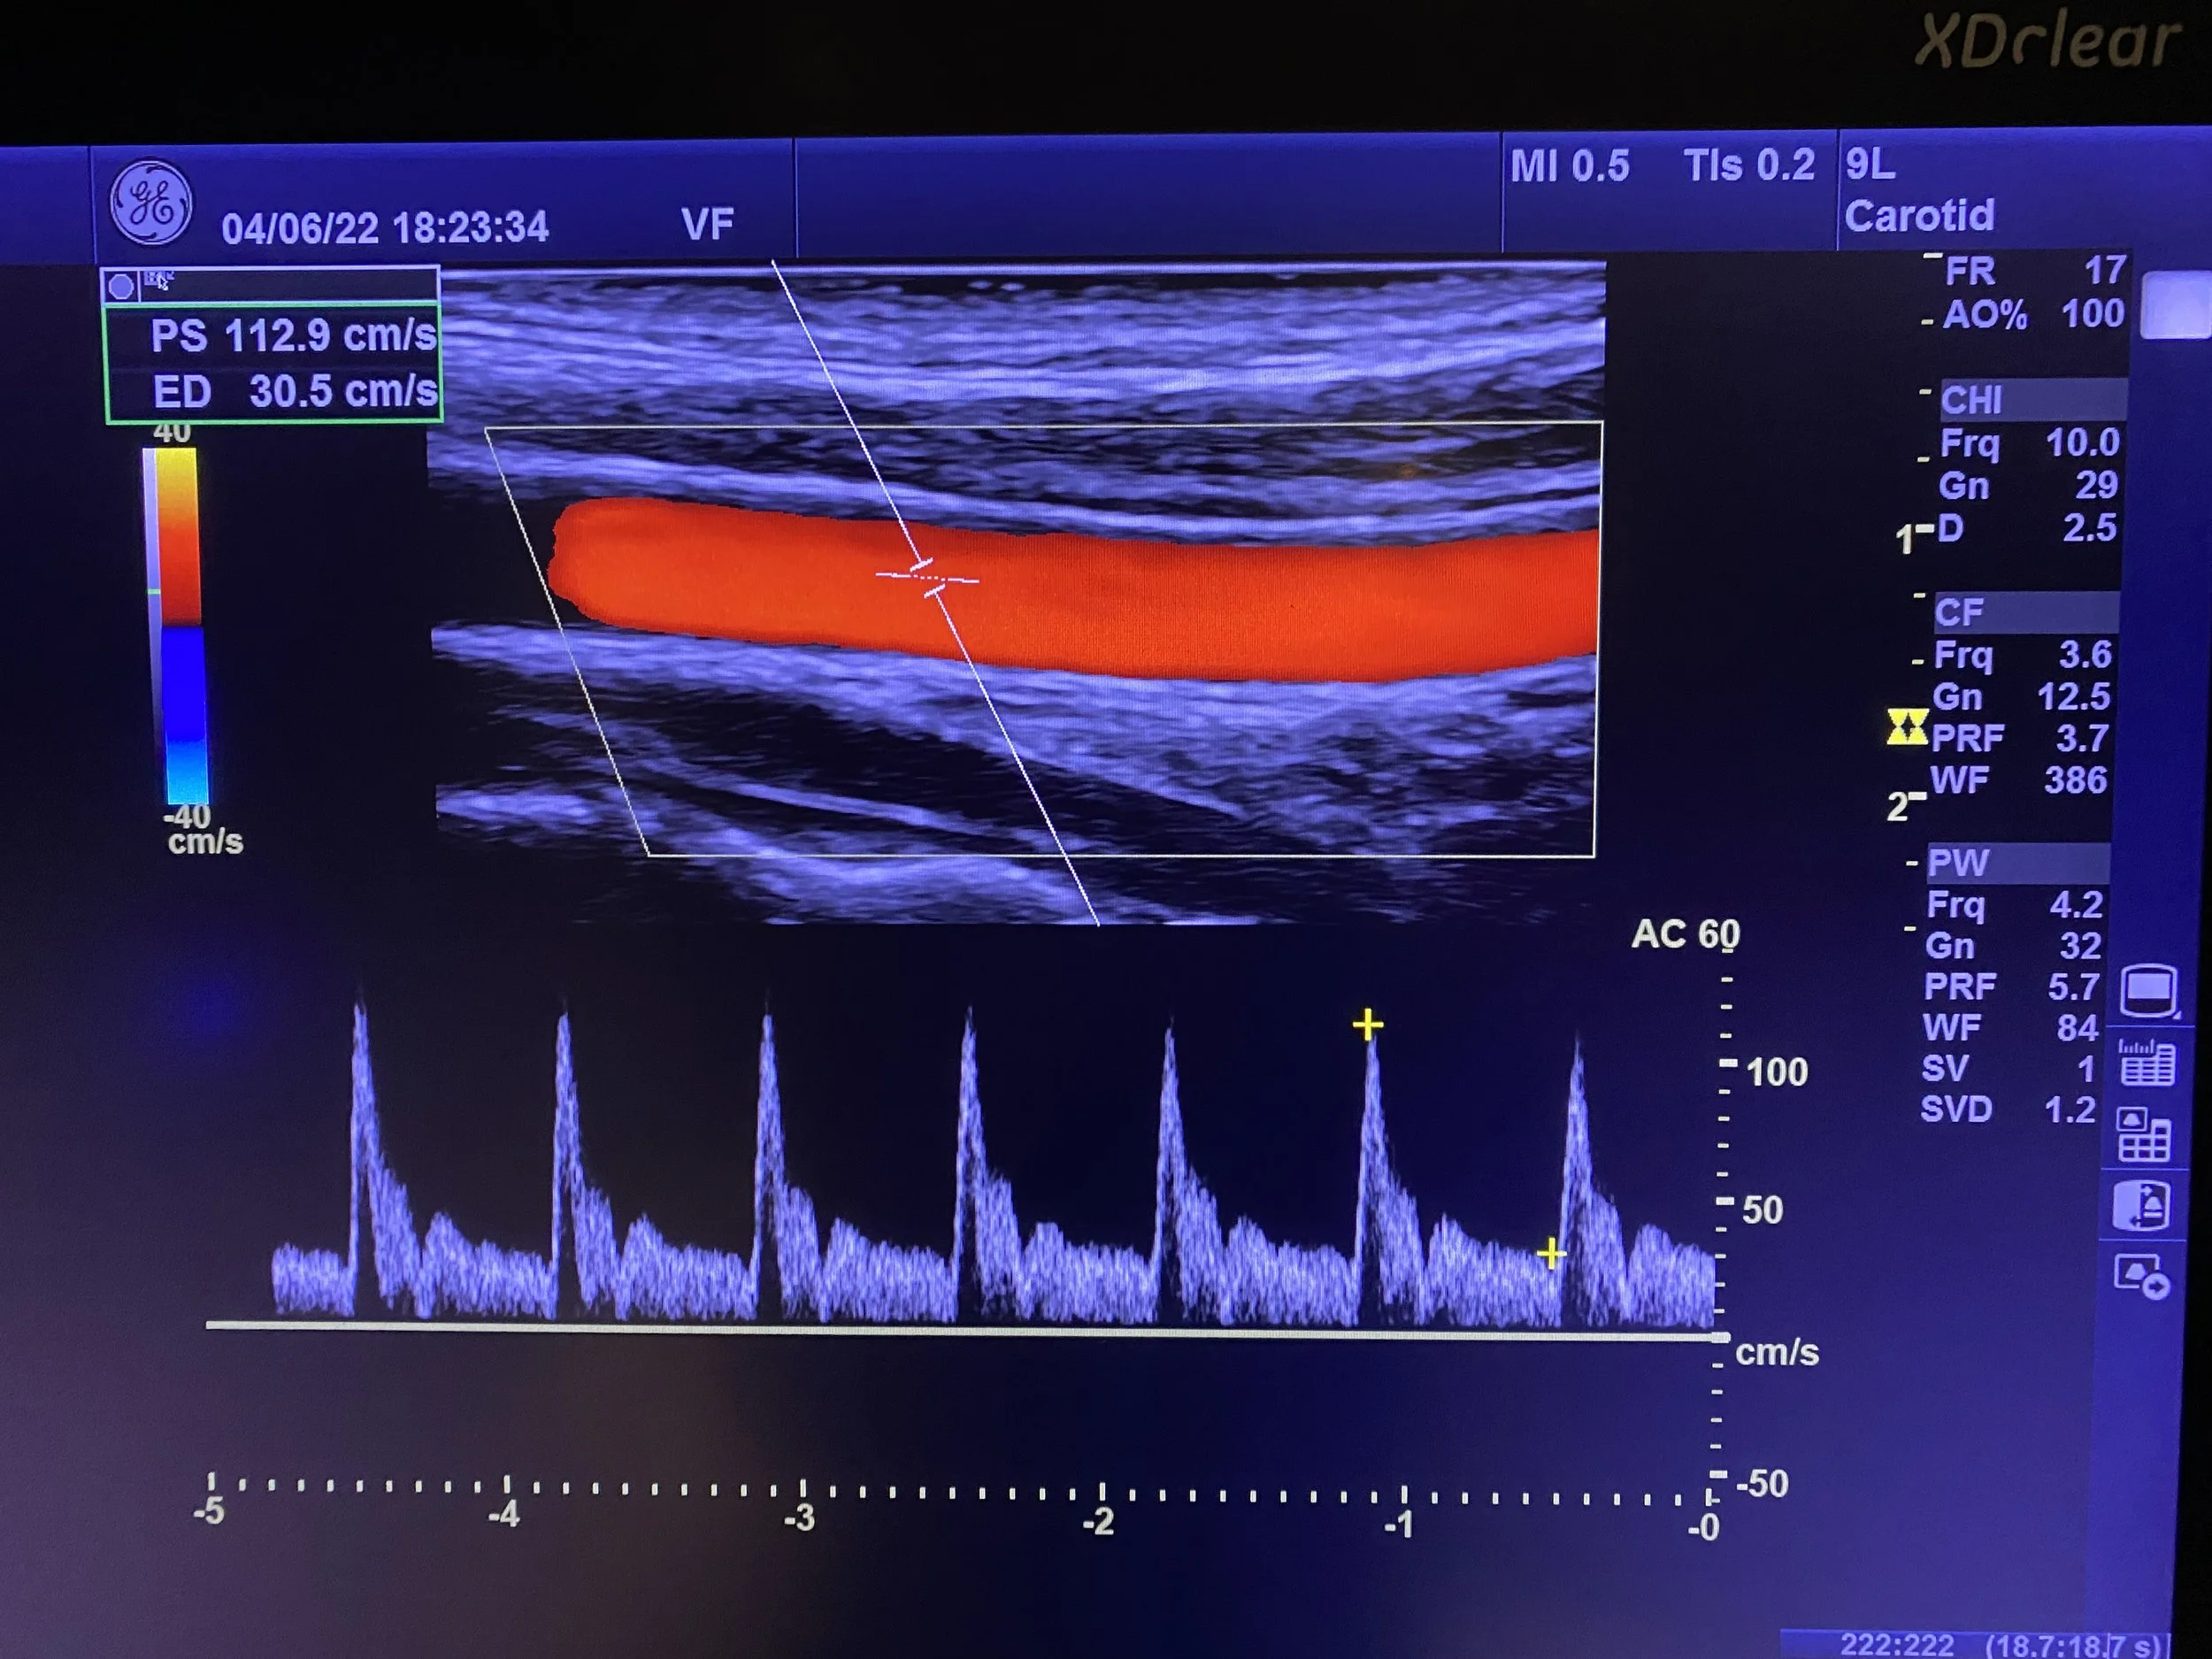

• Carotid Doppler